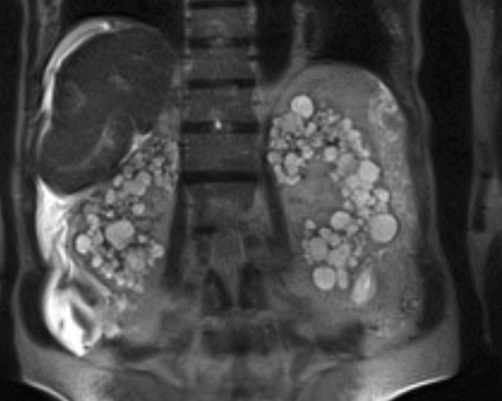

ADPKD

Autosomal Dominant Polycystic Kidney Disease

- Polykysose Dominante

- Adulte

- Kystes milimétriques à centimétriques

- Elargissement rénal

- Kystes Hépatiques ++ (mais aussi pancréas, rate, gonades)

- Associé à Hypertension (Chercher anévrismes du polygone de Willis)

- Pas associé au RCC, mais vu qu’ils finissent sous dialyse finalement le risque est “augmenté”

- Mesurer la volumétrie → Le risque c’est les patients progresseur rapide en volume